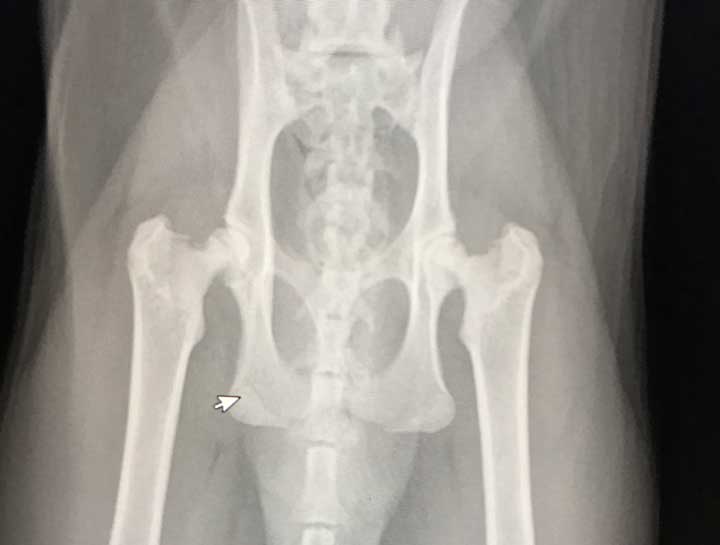

Pet Digital Radiology

Digital x-rays assist in diagnosing illness & injury.